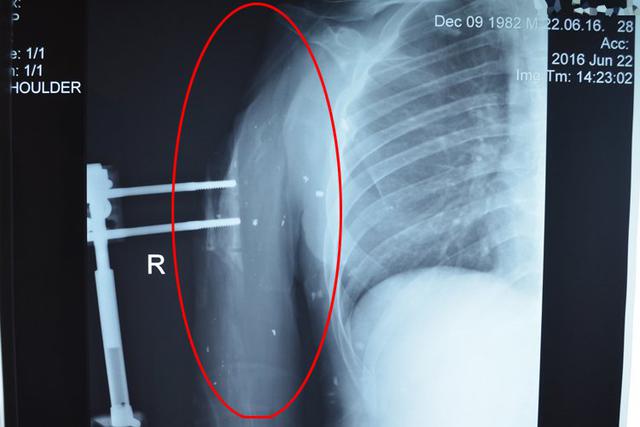

"Роман - один із наших найважчих пацієнтів. У хлопця практично немає плеча - тіло важко пошкодило близьким вибухом міни. Уламки розірвали м'язи й кістку, на даний момент у Романа фактично відсутній плечовий суглоб. Хлопець пройшов через кому і близько десятка операцій у державних і військових госпіталях, і єдине, що може запропонувати сучасна медицина далі - штучний суглоб, артродез - жорстко прифіксовані залишки кістки до лопатки, або навіть ампутація. Звичайно, при жодному з варіантів про відновлення повністю не йдеться. Тепер єдина надія Романа - клітинні технології, які повинні наростити фрагменти суглобових кісток, яких бракує, і повернути хлопця до нормального життя", - розповідають вони.